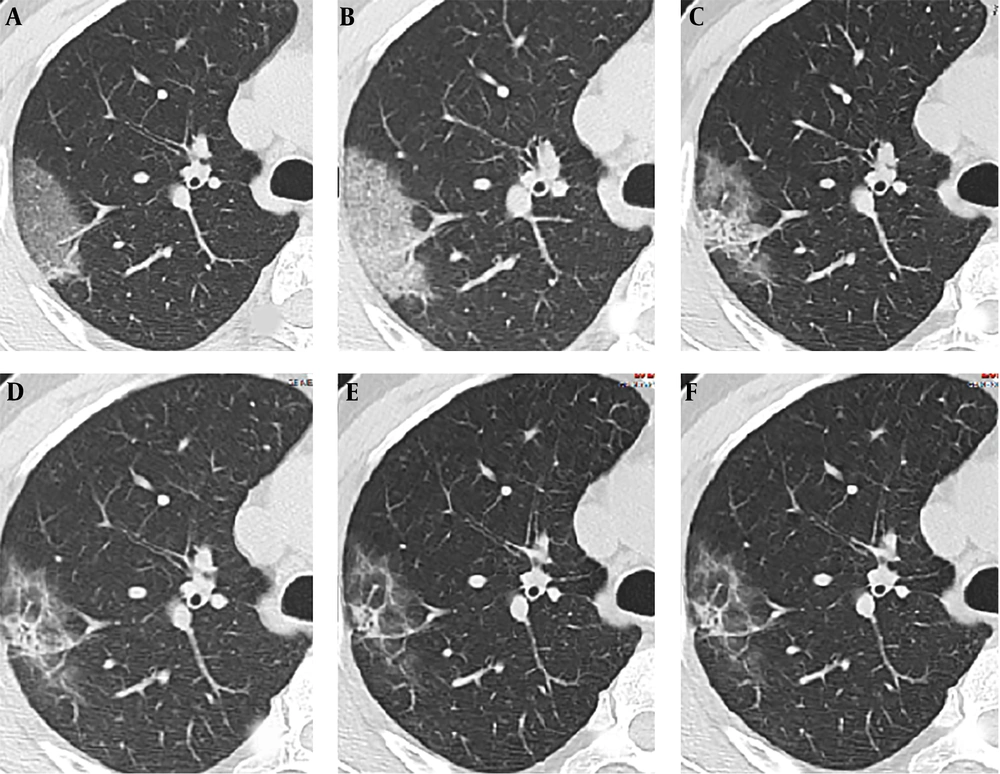

4.3. Follow up CT

CT image findings of a 42-year-old male on the 2nd (stage-1), 6th (stage-2), 9th, 12th, 16th and 21th (stage-3) day demonstrated crazy paving GGO pattern (pattern D) (A), crazy paving GGO mixed with partial consolidation pattern (pattern E) (B), consolidation pattern (pattern F) (C, D) and minimal parenchymal bands pattern (pattern H) (E) and multiple GGO pattern (pattern B) (F) respectively.